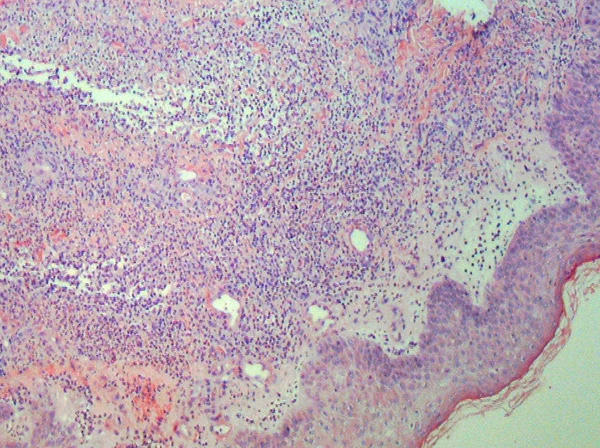

Классическая гистологическая картина синдрома Свита характеризуется плотным диффузным нейтрофильным инфильтратом, преимущественно локализованным в сетчатом слое дермы. В интерстициальном пространстве часто выявляются остатки разрушенных ядер нейтрофилов (лейкоклазия, «ядерная пыль»), а также выраженный отёк сосочкового слоя дермы[6].

Истинные признаки лейкоцитокластического васкулита, как правило, отсутствуют. В отдельных случаях отмечается периваскулярное расположение инфильтрата и расширение капилляров[6][9].

Клеточный состав инфильтрата представлен преимущественно полинуклеарными нейтрофилами; в меньшем количестве могут присутствовать лимфоциты, мононуклеары, эозинофилы и гистиоциты. Инфильтрация может носить как диффузный, так и периваскулярный характер, иногда распространяясь вокруг придатков кожи[1][9].

Эпидермис в большинстве случаев остаётся интактным. Однако могут выявляться неспецифические изменения, включая слабовыраженный акантоз, очаговую вакуолизацию клеток шиповатого слоя, спонгиоз, а также мелкофокусные субэпидермальные пузыри, содержащие нейтрофилы, и редкие субкорнеальные пустулы[7][1].